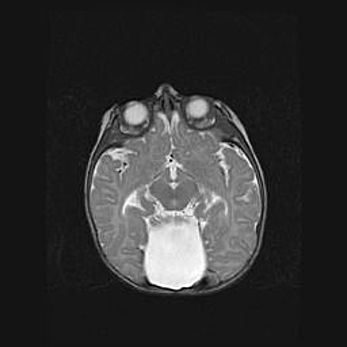

Мальформация Денди-Уокера. Киста задней черепной ямки.

Агенезия мозолистого тела.

Возраст: 2,5 месяца

Вес: 2420 г

Пол: женский

Окружность головы: 37 см

Срок гестации: 32 недели

Мальформация Денди—Уокера — редкий вид патологии ЦНС, представляющий собой врожденный порок развития каудального отдела ствола и червя мозжечка, ведущий к неполному раскрытию срединной (Мажанди) и латеральных (Лушка) апертур IV желудочка мозга. Для этогно синдрома характерна триада симптомов: гипотрофия червя мозжечка и/или полушарий мозжечка, кисты задней черепной ямки, гидроцефалия различной степени. В 70% случаев порок сочетается и с другими аномалиями головного мозга, в частности с агенезией мозолистого тела.